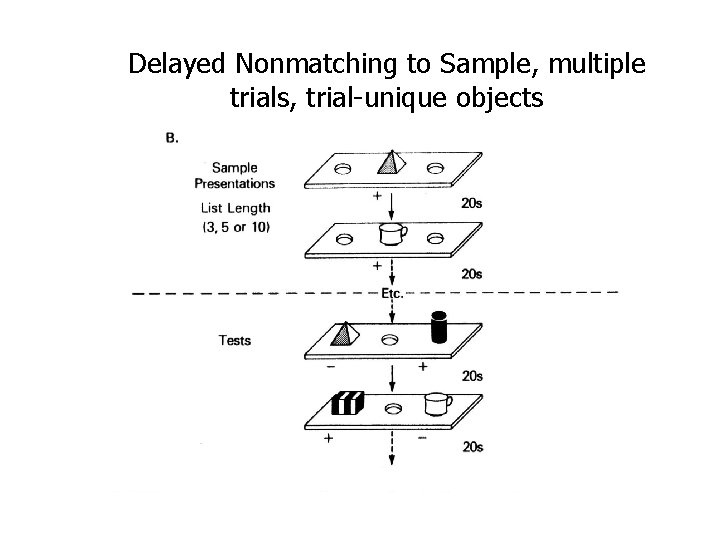

Delayed Nonmatching to Sample

Delayed Nonmatching to Sample, multiple trials, trial-unique objects